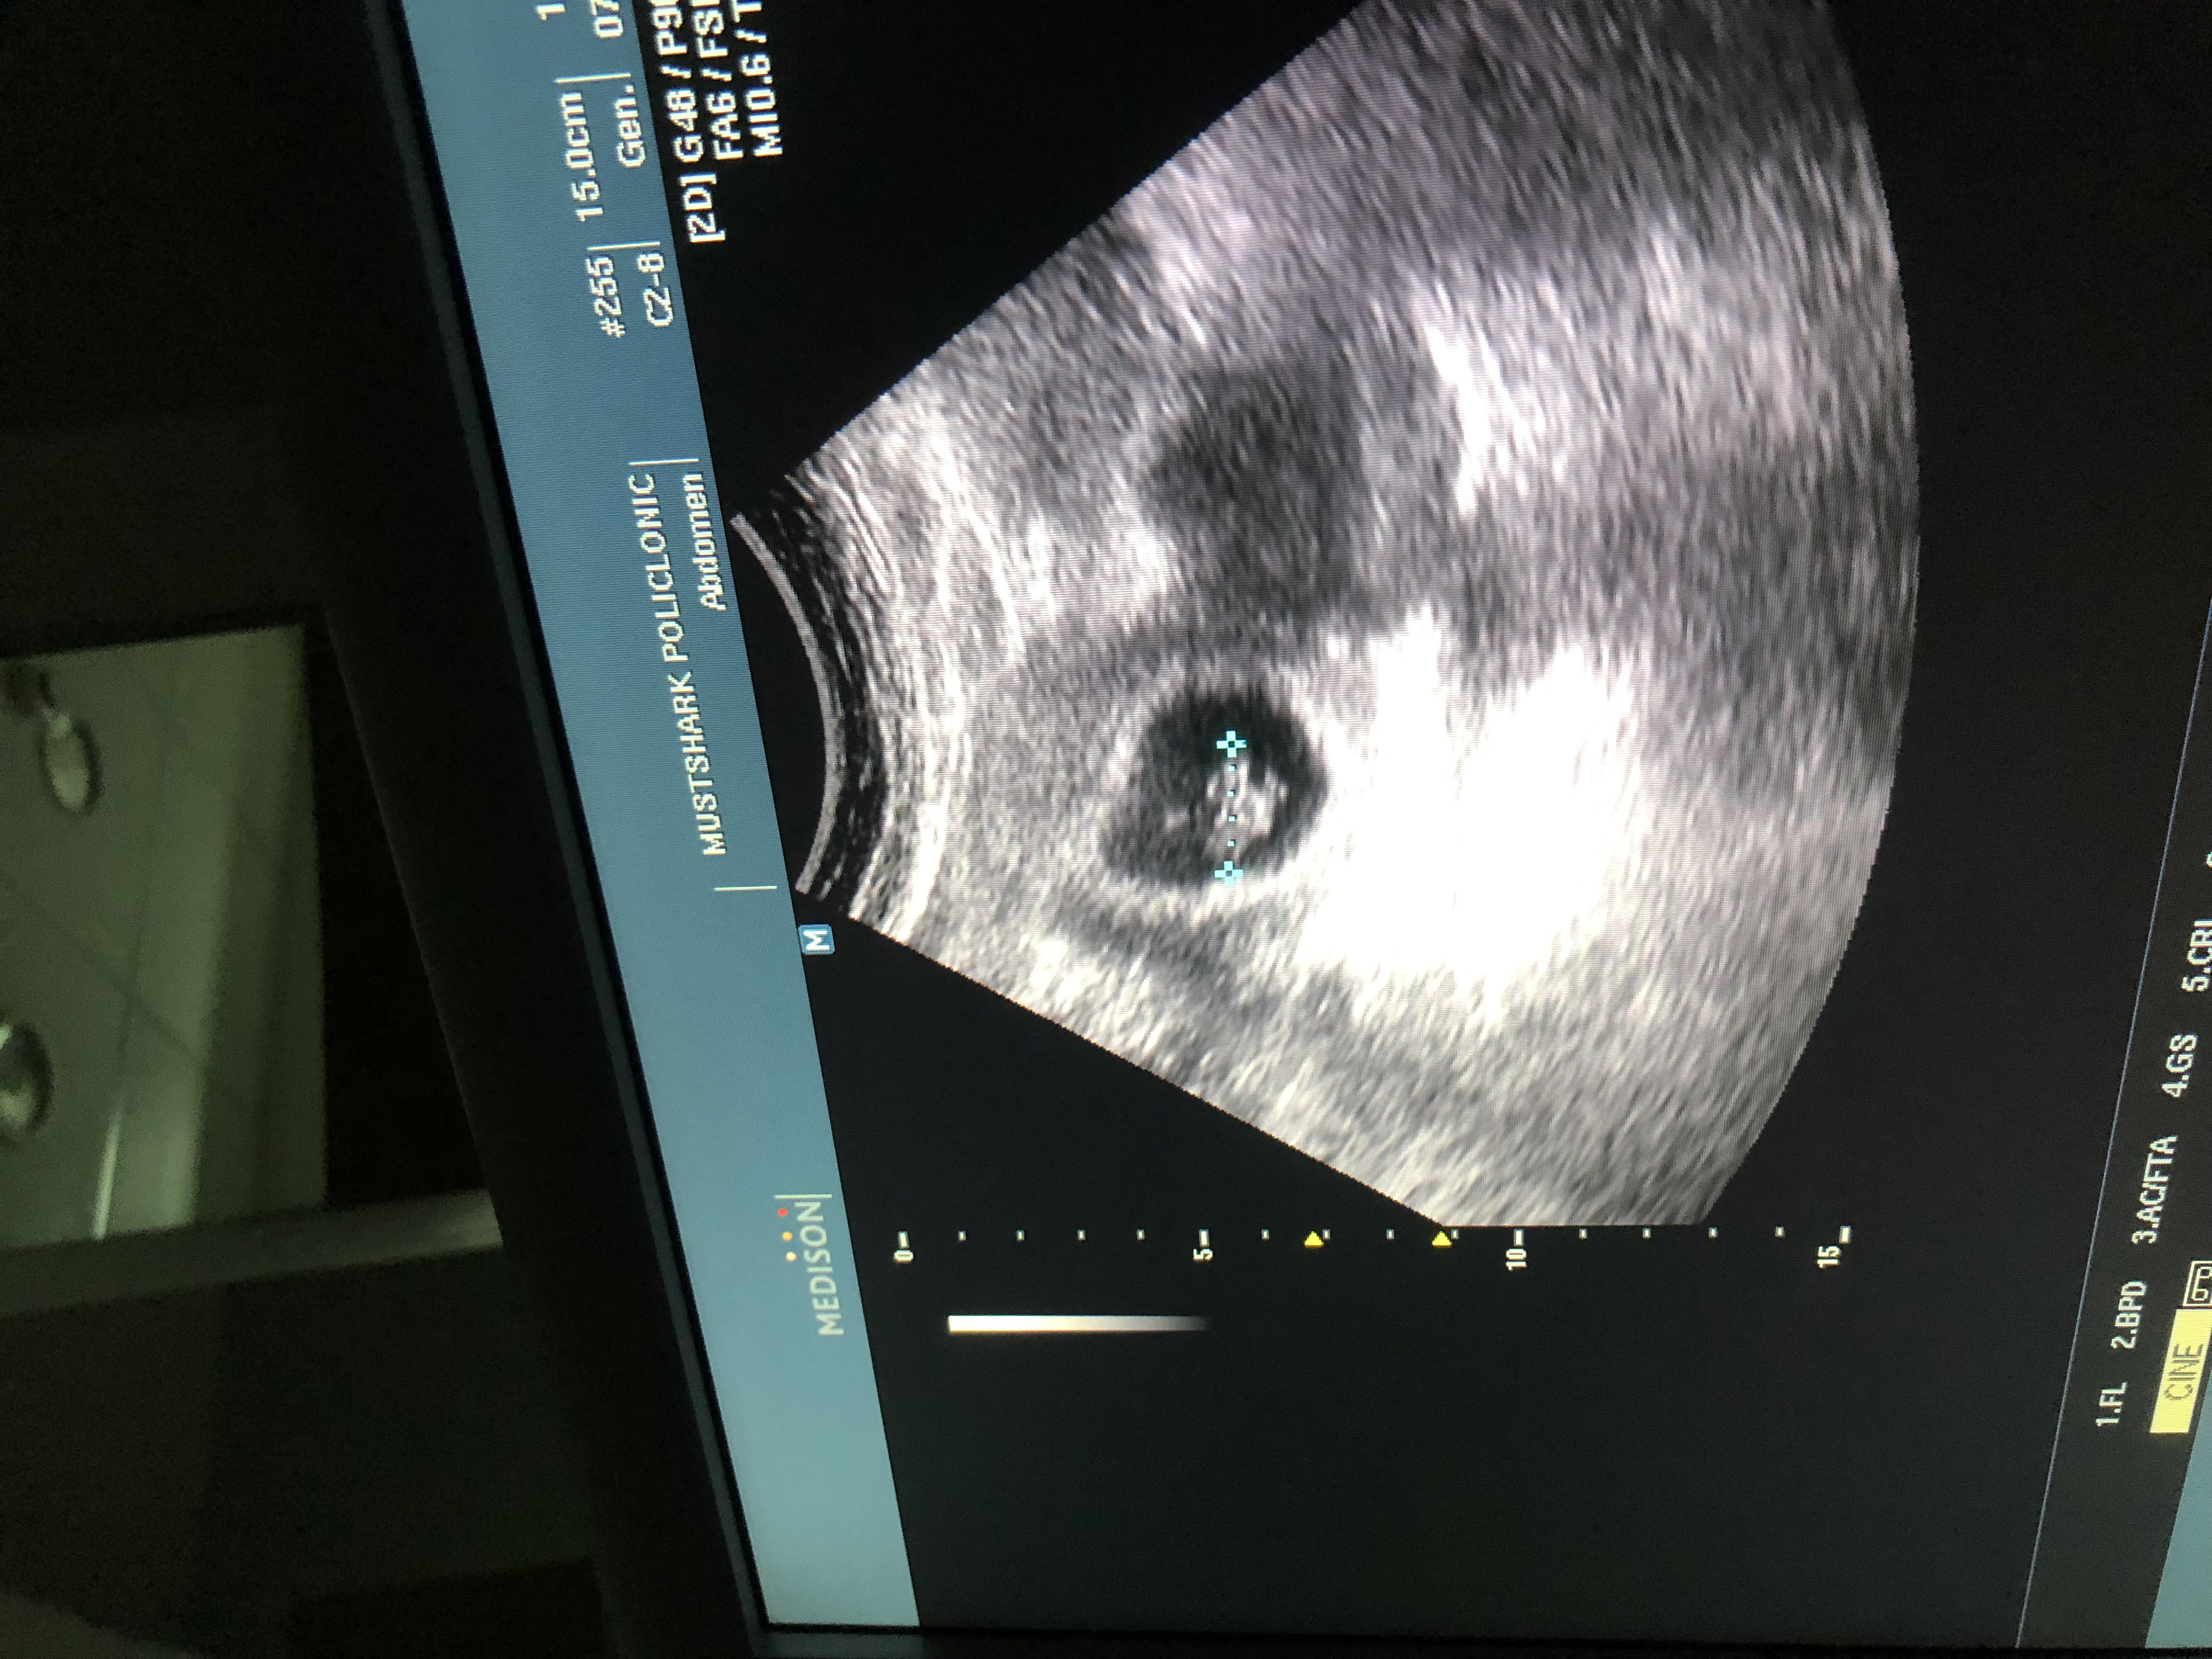

الدكتوره حاسبه لي اني بالاسبوع الثامن وانا حسبتي اني بنهاية الاسبوع الخامس حسبت عن طريق وقت الاتصال

المهم هذي قرائات السونار اللي تقدر تفيدني الله يسعدها لاني مافهمت في شيء مكتوب اسبوع خامس وشيء اسبوع ثامن خفت

السلام عليكم بنات الدكتوره حاسبه لي اني بالاسبوع الثامن وانا حسبتي اني بنهاية الاسبوع الخامس حسبت عن طريق وقت الاتصال المهم هذي قرائات السونار اللي تقدر تفيدني الله يسعدها لاني مافهمت في شيء مكتوب اسبوع خامس وشيء اسبوع ثامن خفت ريحوني الله يسعدكم / وهل نظرية رمزي توضح جنس الجنين اللحين هذي هي الصور https://j.top4top.io/p_2116c78lu0.jpeg https://k.top4top.io/p_2116hnh621.jpeg